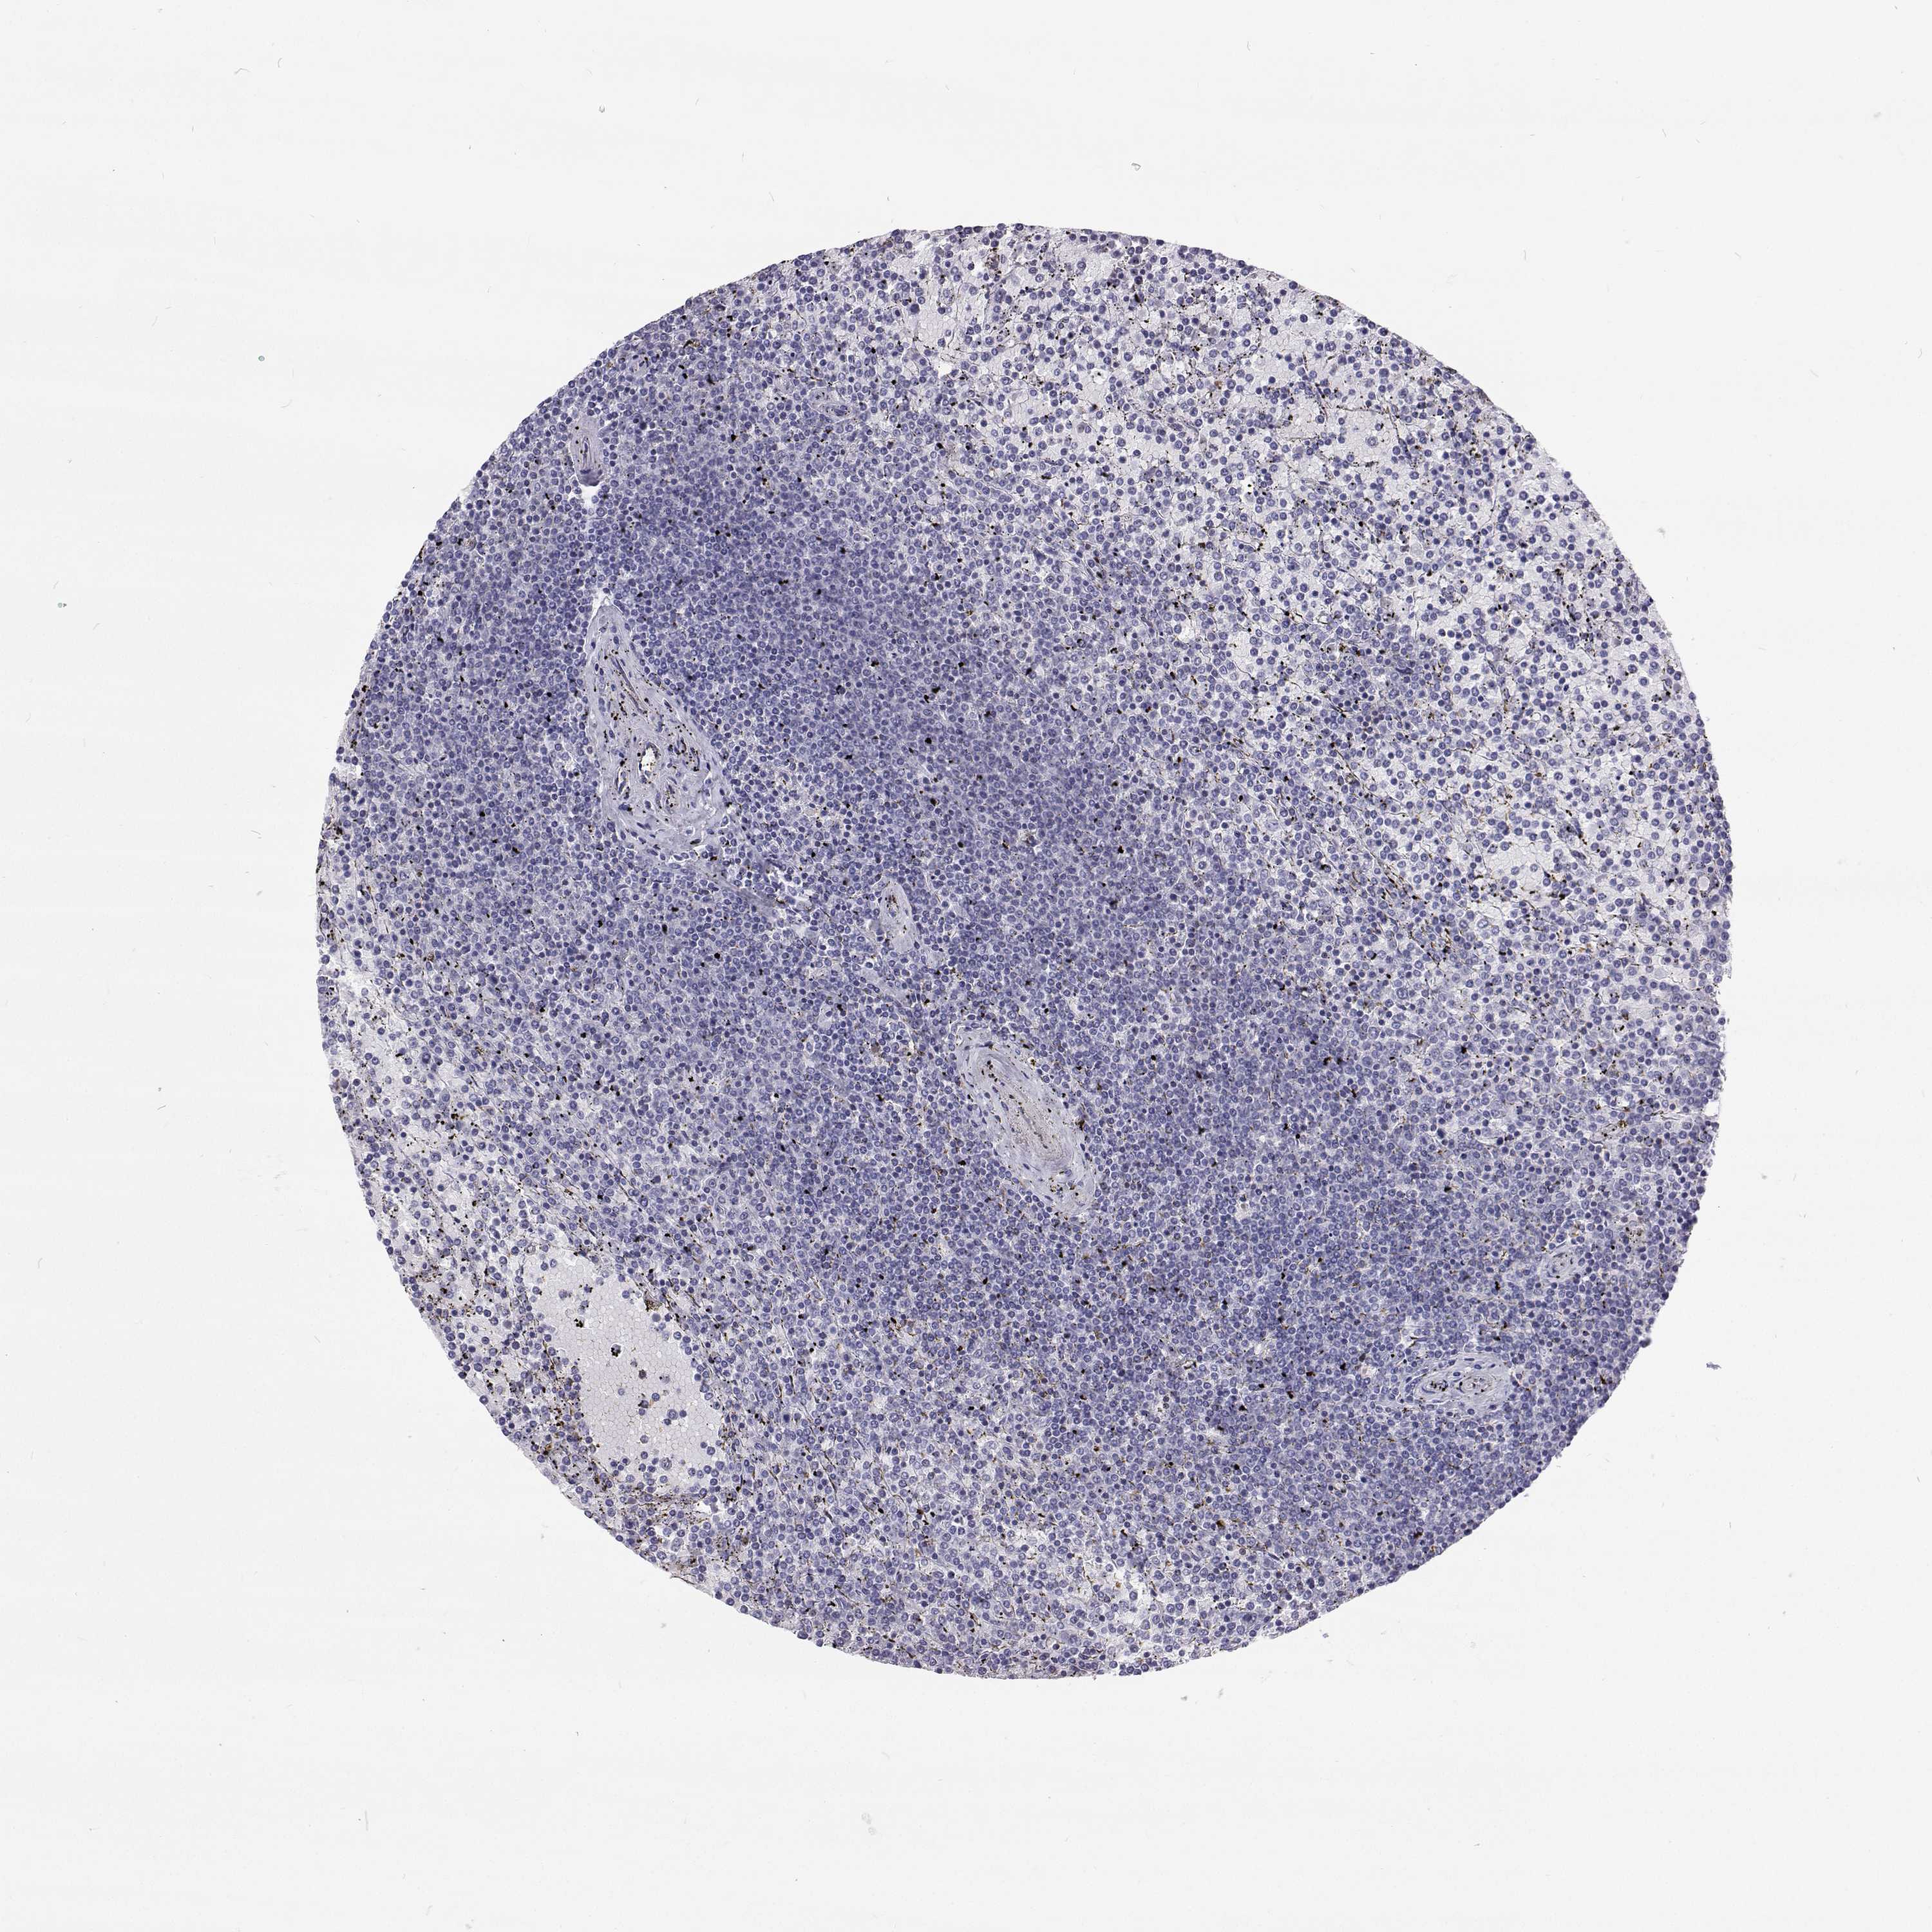

LYMPHOMA - Protein expressioni

A mouse-over function shows sample information and annotation data. Click on an image to view it in a full screen mode. Samples can be filtered based on level of antibody staining by selecting one or several of the following categories: high, medium, low and not detected. The assay and annotation is described here.

Antibody stainingi

Antibody staining in the annotated cell types in the current human tissue is reported as not detected, low, medium, or high, based on conventional immunohistochemistry profiling in selected tissues. This score is based on the combination of the staining intensity and fraction of stained cells.

Each image is clickable and will lead to virtual microscopy that enables deeper exploration of all samples and also displays staining intensity scores, fraction scores and subcellular localization as well as patient and tissue information for each sample.

Antibody HPA035472

Antibody HPA035473

Antibody HPA064835

Malignant lymphoma, non-Hodgkin's type, Low grade

Malignant lymphoma, non-Hodgkin's type, High grade

Hodgkin's disease, NOS